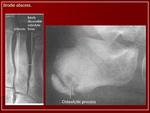

Абсцесс Броди в метафизе большеберцовой кости.

Абсцесс Броди — своеобразный первично-хронический гематогенный остеомиелит, при котором воспалительный очаг локализуется на ограниченном участке, чаще в проксимальном метафизе большеберцовой кости (рис.). Наблюдается преимущественно у лиц мужского пола в молодом возрасте. Возбудителем процесса является золотистый стафилококк или тифозная палочка. Протекает абсцесс Броди доброкачественно, иногда незаметно для больного и обнаруживается случайно на рентгенограмме, сделанной по какому-нибудь другому поводу. Иногда бывают обострения, появляются боли, усиливающиеся при надавливании на очаг, повышается температура тела. Свищи никогда не образуются.

Рентгенологически обнаруживают полость с чёткими склерозированными контурами, при обострении периостальные наслоения, остеосклероз.

Абсцесс Броди встречается довольно редко, имеет, однако, немалое практическое значение. Знакомство с этим заболеванием для рентгенолога обязательно, так как точное распознавание, за которым должно следовать радикальное хирургическое вмешательство, возможно только при помощи рентгеновых лучей.

Особенностью гнойника Броди является локализация в губчатом костном веществе, причем практически почти никогда не поражаются мелкие или плоские кости, а исключительно большие трубчатые кости, а именно метафизарные концы. На первом месте по частоте заболевания стоят суставные концы костей, образующих коленный, голеностопный и локтевой суставы. Самым типичным и излюбленным местом локализации гнойника является большеберцовая кость, на долю которой выпадает 80% всех случаев, причем проксимальный метафиз поражается чаще, чем дистальный. Гнойник предпочтительно располагается поверхностно, под корковым слоем кости.

Рис. 208. Хронический костный абсцесс Броди в верхнем метафизе большеберцовой кости.

Рентгенологическое исследование имеет решающее диагностическое значение. Все детали патологоанатомической картины абсцесса Броди передаются в точности и на рентгеновских снимках (рис. 207 и 208). Изолированная, правильной округлой формы полость, без секвестра, с резко ограниченными гладкими внутренними контурами, расположенная среди склерозированного губчатого вещества, на типичном месте — в метафизарном конце большой трубчатой кости, слегка утолщенной благодаря периостальным наслоениям, — эта рентгенологическая картина при поддержке клинических симптомов разрешает диагностическую задачу. При этом следует учесть, что между, так сказать, классическим типичным абсцессом Броди и другими формами хронического остеомиелита бывают и переходные формы — и по местоположению, размерам, форме, характеру реактивных изменений в окружности, секвестрации и т. д. Это ведь в природе вещей: классификация показывает всегда несколько условно типичное, жизнь преподносит многообразие, не укладывающееся в строгую жесткую схему. Никоим образом не следует злоупотреблять диагнозом абсцесса Броди и ставить его расширительно, чуть ли не во всех случаях более или менее ясно выраженной полости при обычном хроническом остеомиелите: абсцесс Броди — это совершенно определенное клинико-рентгено-анатомическое понятие, это четкая нозологическая единица, и диагноз оправдан лишь в тех случаях, когда рентгенологическая картина удовлетворяет всем вышеперечисленным критериям.